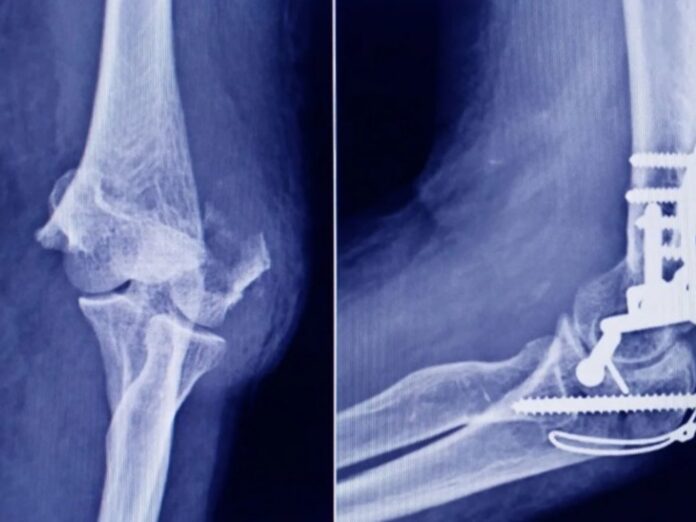

La Administración Nacional de Medicamentos, Alimentos y Tecnología Médica (ANMAT) ha emitido una alerta tras descubrir un tornillo utilizado en cirugías traumatológicas que se comercializa de forma ilegal. Este tornillo, procedente de la firma Stryker Corporation, fue encontrado en una ortopedia en San Miguel de Tucumán durante una inspección rutinaria.

El tornillo en cuestión, que mide 10 mm x 28 mm, fue confirmado como falsificado tras un análisis de características clave. La representante técnica de Stryker señaló que el producto carecía de la fecha de vencimiento que caracteriza a los artículos originales, una de las principales diferencias detectadas.

Al comparar ambos productos, se observó que el tornillo original es de color gris opaco, mientras que el falsificado es incoloro y no ha sido esterilizado adecuadamente. Mientras que Stryker utiliza radiación gamma para la esterilización, el tornillo falso parece haber sido tratado con vapor o formaldehído, lo que compromete su seguridad.